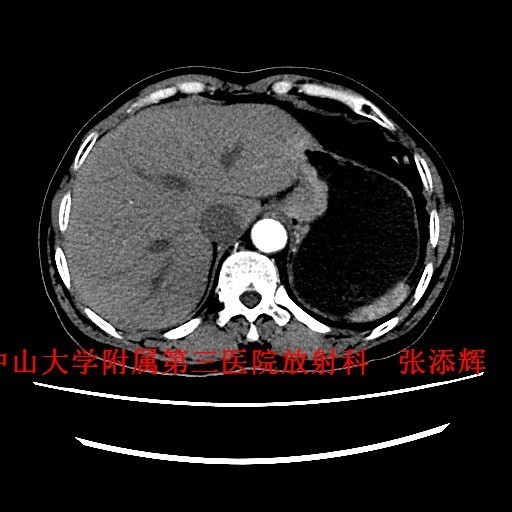

查体:全身浅表淋巴结未触及肿大。腹平软,无压痛、反跳痛。 辅查:1、胃镜:贲门Ca?;2、上腹部CT示:贲门胃底癌,浸润胃壁全层,小网膜囊多发稍大淋巴结。

诊断:贲门癌 治疗:排除手术禁忌征后,全麻下行“腹腔镜下根治性全胃切除术”。术中及术后病理诊断为“中-低分化腺癌,浸润胃壁全层,1/61枚淋巴结转移,分期T3NIM0,ⅡB期”。

讨论:贲门癌发病率和病死率均较高,临床上其诊断主要依靠胃镜检查+病理活检,然而CT检查也是贲门癌必不可少的术前检查,术前CT不仅能了解贲门癌病变局部情况,还可以观察周围结构及远处转移的情况,特别是对于淋巴结的转移,贲门癌淋巴结转移多位于贲门旁、胃小弯、胃左动脉及腹腔动脉周围淋巴结,平时读片是应该多注意这些部位的淋巴结是否肿大。 参考文献:Stein HJ,Feith M,Siewert JR. Cancer of the esophagogastric junction [J].Surgical Oncology,2000,9(01):35-41 .doi:10.1016/S0960-7404(00)00021-9 .